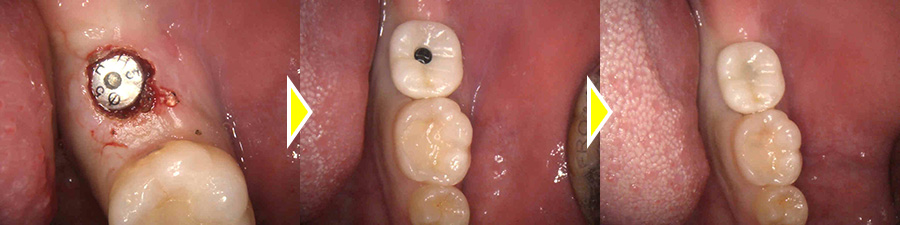

インプラント体と骨がしっかりと結合するのを待ち、型取りを2回行い、アバットメントと上部ジルコニアをセットしました。

上部構造(人工歯)の装着・治療完了

術後は奥歯で硬いものもしっかりと噛むことができるようになり、機能的にも審美的にも大変満足していただいています。

現在はセルフケアと定期的なクリーニングを行っており、セットした時と変わらずキレイな状態を保つことができています。